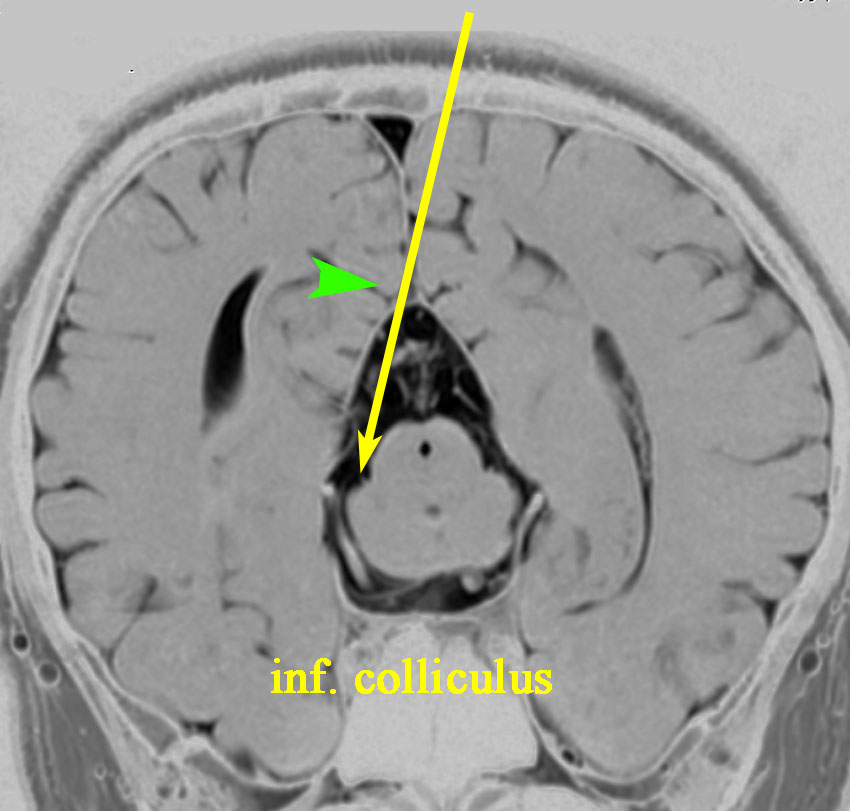

5. 後交連 PC posterior commissure

松果体腫瘍が上丘を圧迫して眼球運動障害を呈することは良く知られています。実際に松果体腫瘍の手術で上丘を損傷することはほとんどなく,術後に残る微妙な複視は,後交連 (PC posterior commissure) の損傷によって生じます。左の画像のように,松果体腫瘍が第3脳室方向に伸展増大すると後交連を圧排して,後交連は扁平化します。手術中には,上丘の奥に,上丘と連続して白く薄い脆弱な白質組織が見えます。それが後交連です。左右にも長い白質組織なので,腫瘍底面から非常に慎重に剥離する必要があります。後交連の剥離が終わると第3脳室内の髄液腔に抜けます。